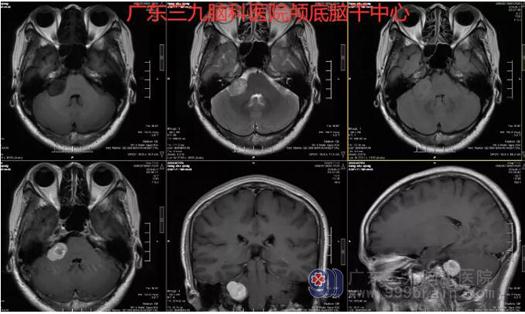

图1:术前MR示右侧桥小脑角区示一团片状长T1长T2异常信号影,FLAIR序列呈高信号,大小约21mm×19mm,增强后病变呈不均匀明显强化,邻近听神经增粗、轻度强化,邻近脑膜轻度增厚、强化。右侧小脑半于及桥臂轻度受压。